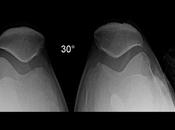

Artroplastia en rodilla izquierda.

RADIOGRAFIA AP, LATERAL Y AXIALES DE RODILLAS LAS PROYECCIONES RADIOLÓGICAS MUESTRAN LOS SIGUIENTES HALLAZGOS: Los tejidos, simétricos, sin evidencia de... Leer el resto